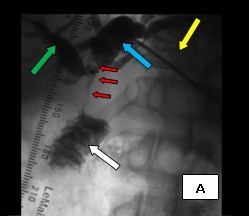

The first case (images A, B, and C), was an elderly man who came to me from a nursing home with advanced carcinoma of his common bile duct that severely narrowed the duct. The string of contrast outlining the very narrow common bile duct (red arrows, image A) and the dilated ducts above the narrowing (green and blue arrows, image A) testify to the severity of the disease. His left hepatic duct (blue arrow, image A) had been percutaneously decompressed elsewhere with a drainage catheter (yellow arrow, image A), but he remained jaundiced and ill.

So, coming through a fresh percutaneous access on his right side (red arrow, image B) and through the drainage catheter already in his left hepatic duct (blue arrow, image B), I concurrently deployed stents across the obstructed confluence of the hepatic ducts and across the common bile duct. The effect of the treatment is evident by comparing images A and C: decompression of the dilated right and left hepatic ducts, relief of the critical obstruction of the common bile duct, and quick movement of copious amounts of the injected dye (which correlated with the movement of bile) into the duodenum.